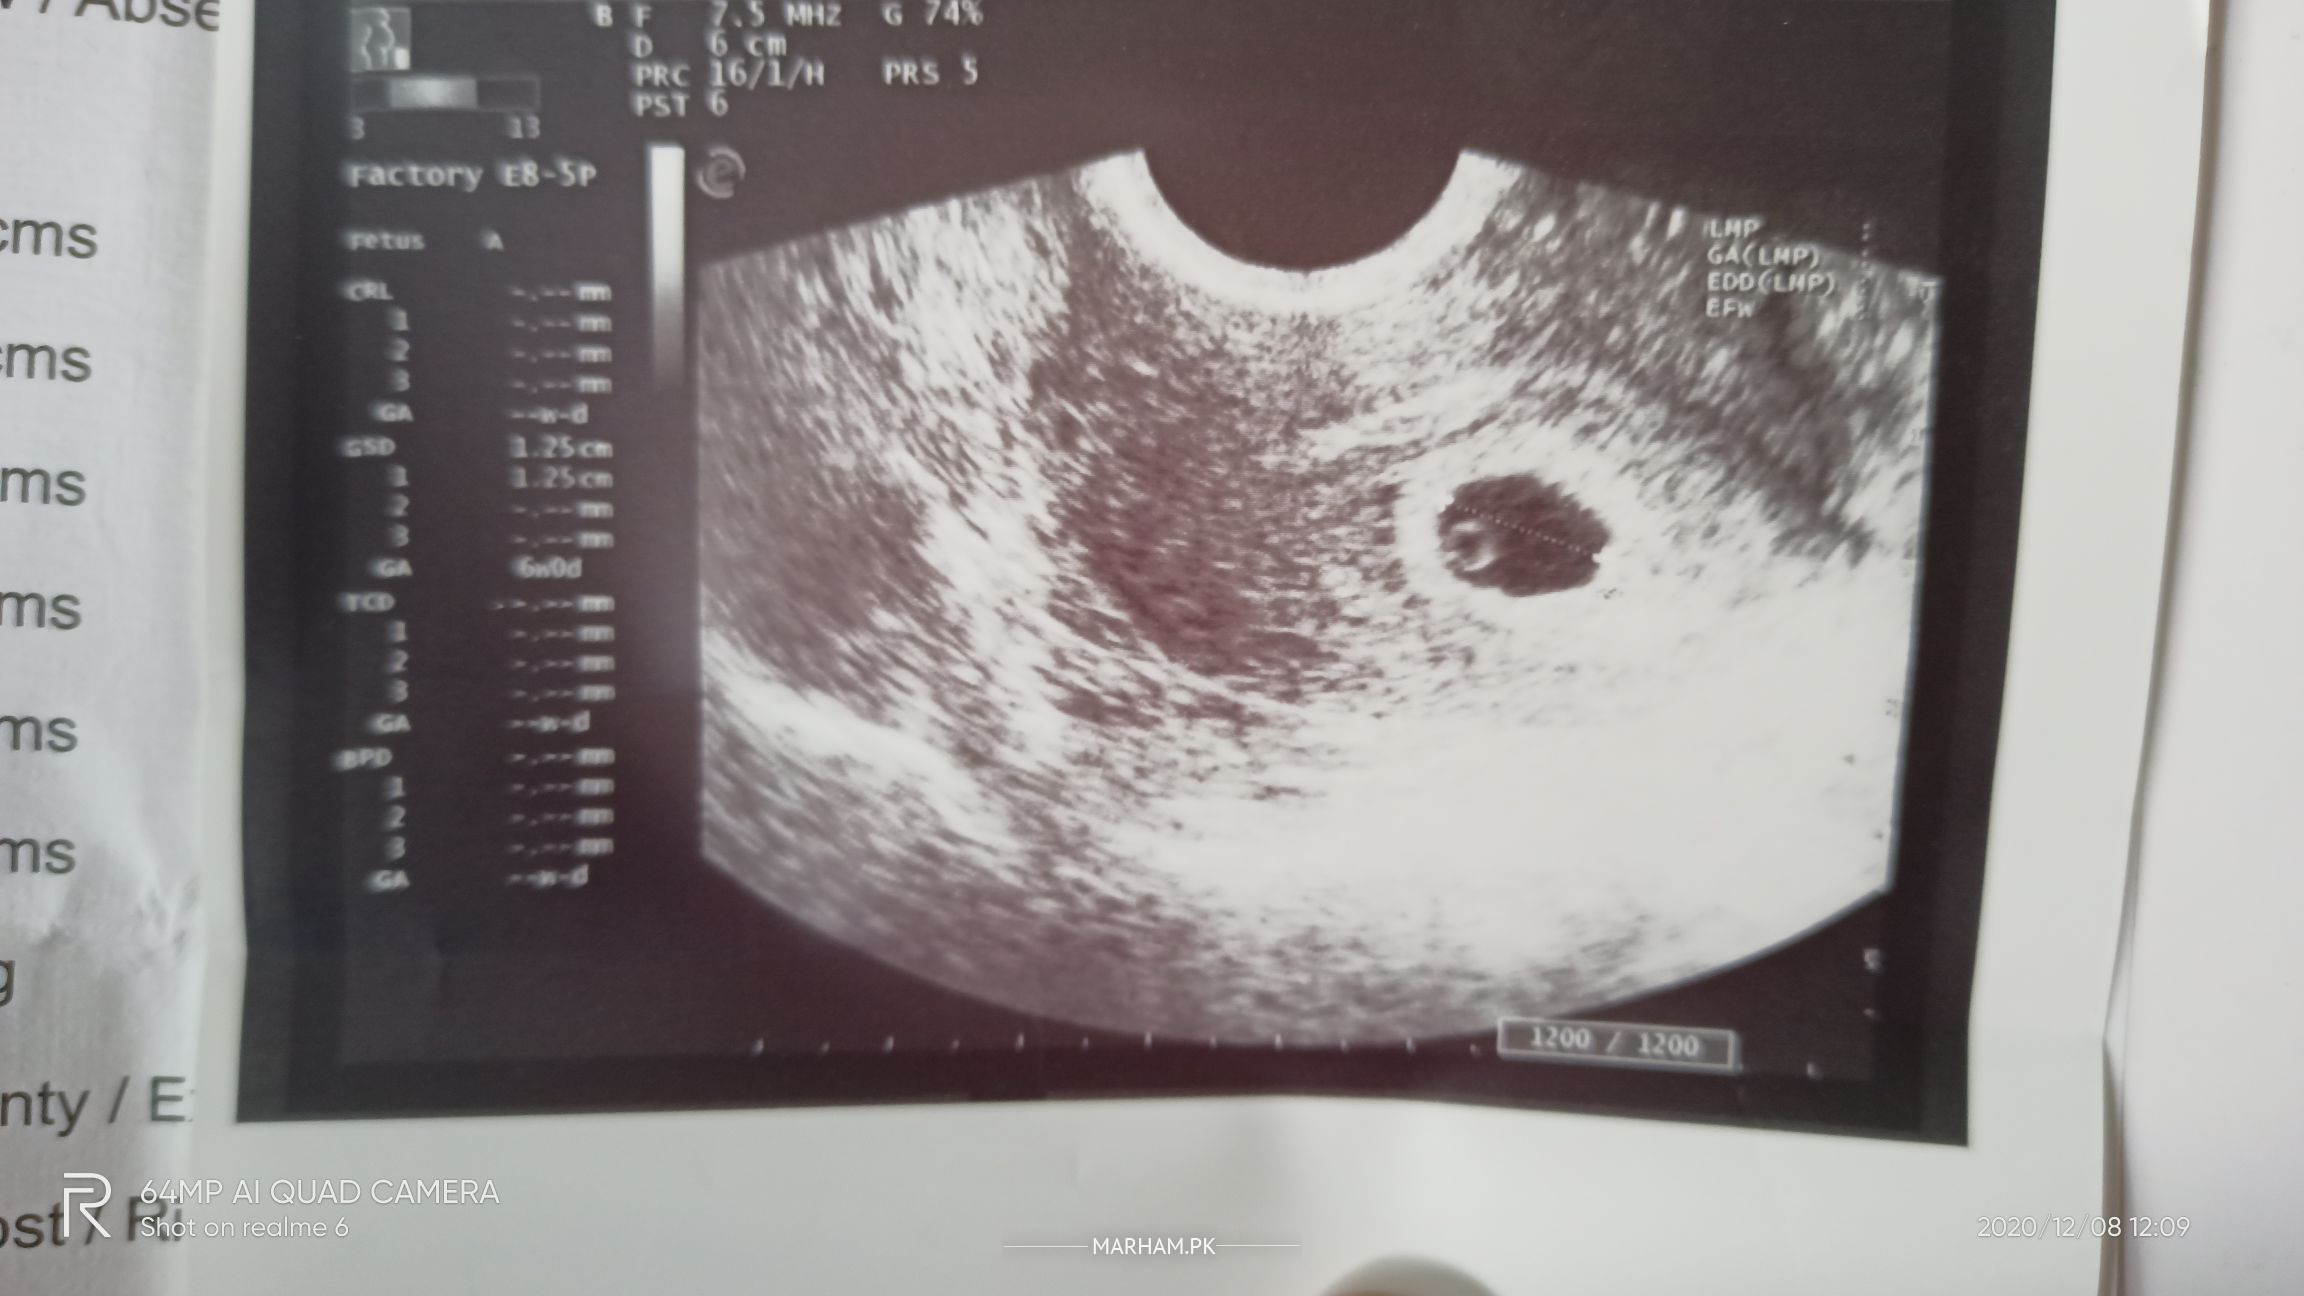

Aslam o alikum meri shadi june 2020 m hoi.. r after shadi 22 Aug ko periods aye nh aye.. shadi se phly mjhy irregular period prob ti nov 4 2020 ko dr k gai periods na hony r breast discharge ki waja se pt strip se chk kia -ve Aya test die fsh lh prolactin etc k r inho ne 5 days k lie maxfol ... or just-N di 5 days bad me gai periods ka poucha inho ne nh hoe mjhy PHR pt strip se chk kia -ve Aya report chk ki a/c to dr mera prolactin zada tha inho ne polymalt syrup 1 week dia me ne lia wo or 1 week bad gai PHR inho ultra sound kia jis ki pic di hy mene inho ne btya pregnancy hy par heartbeat nh arai beta hcg krny ko kha us ki b pic nechy hy PHR repert dekh k heartbeat nh arai hy tu PHR inho ne prescription me injection r tab di hy bhabhi wagra bol rai nh ati heartbeat itni jaldi kuch bol rhy ajati hy dr change KRu m preshan ho gai hm kia kru report dekh k btye sb thk hy??? r medicine m sai le rai?

repeat ultrasound aft two weeks-i can c the yolk sha Allah ethg ll b fine...u can do bhcg now and repeat aft forty eight hours to confirm the viability...

Just wait & repeat your beta hcg after 48 hrs & usg after 1 wk . Book your online consultation for details